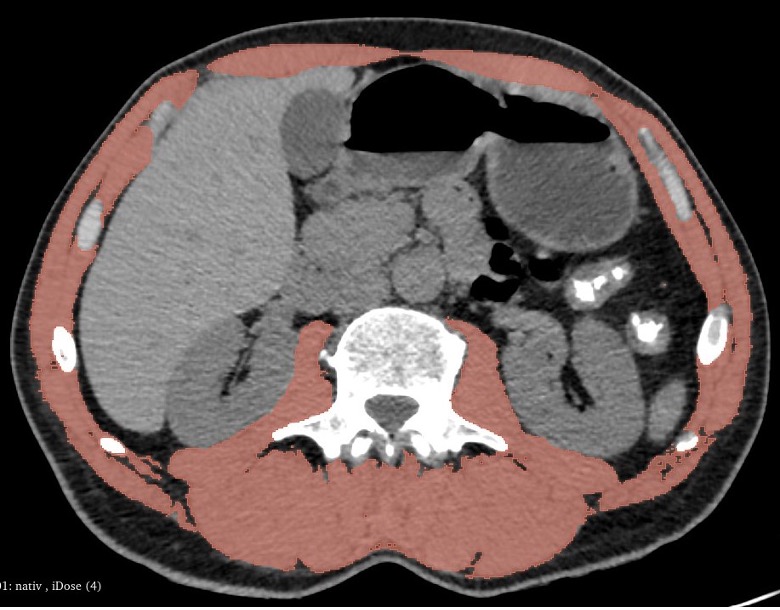

Fig. 2. Preoperative CT scan of a patient with sarcopenia (muscle area 44.5 cm², musculoskeletal index 17 cm²/m²). Muscle tissue is highlighted in red. Axial projection, soft tissue window.

For the purpose of quantitatively evaluating the sarcopenia, we have measured the musculoskeletal index using CT-sarcometry. The measurements were carried out using the axial CT-scans at the level of L3 vertebral bone. The threshold range of the attenuation coefficient varied from -29 to +150 Hounsfield units (HU). A volume of all the skeletal muscles was calculated at the scan zone (paraspinal, major psoas, oblique and rectus abdominal muscles) with excluding other structures. The measurements were carried out by semiautomatic method in the Slicer 5.6.2. software. The segmentation of the image within the pre-set densitometric values was done automatically, while the structures not related to the muscle tissue were removed manually (Fig. 1, 2). The musculoskeletal index was calculated as a ratio of the area of skeletal muscles (cm2) to the square value of the patient height (m2). The threshold values of musculoskeletal index, below which the status of the muscle tissue was considered as sarcopenia, were the classical Prado criteria — 52.4 cm2/m2 for males and 38.5 cm2/м2 for females [15]. For the purpose of simplification of the interpretation of the obtained values, they were presented not as absolute values, but as a ratio of the obtained value to the lower margin of the reference ranges for the given gender (musculoskeletal index). Besides, all the patients at the pre-operative stage had their BMI, body mass and height measured along with the levels of hemoglobin, iron, albumin, transferrin and total protein in blood.